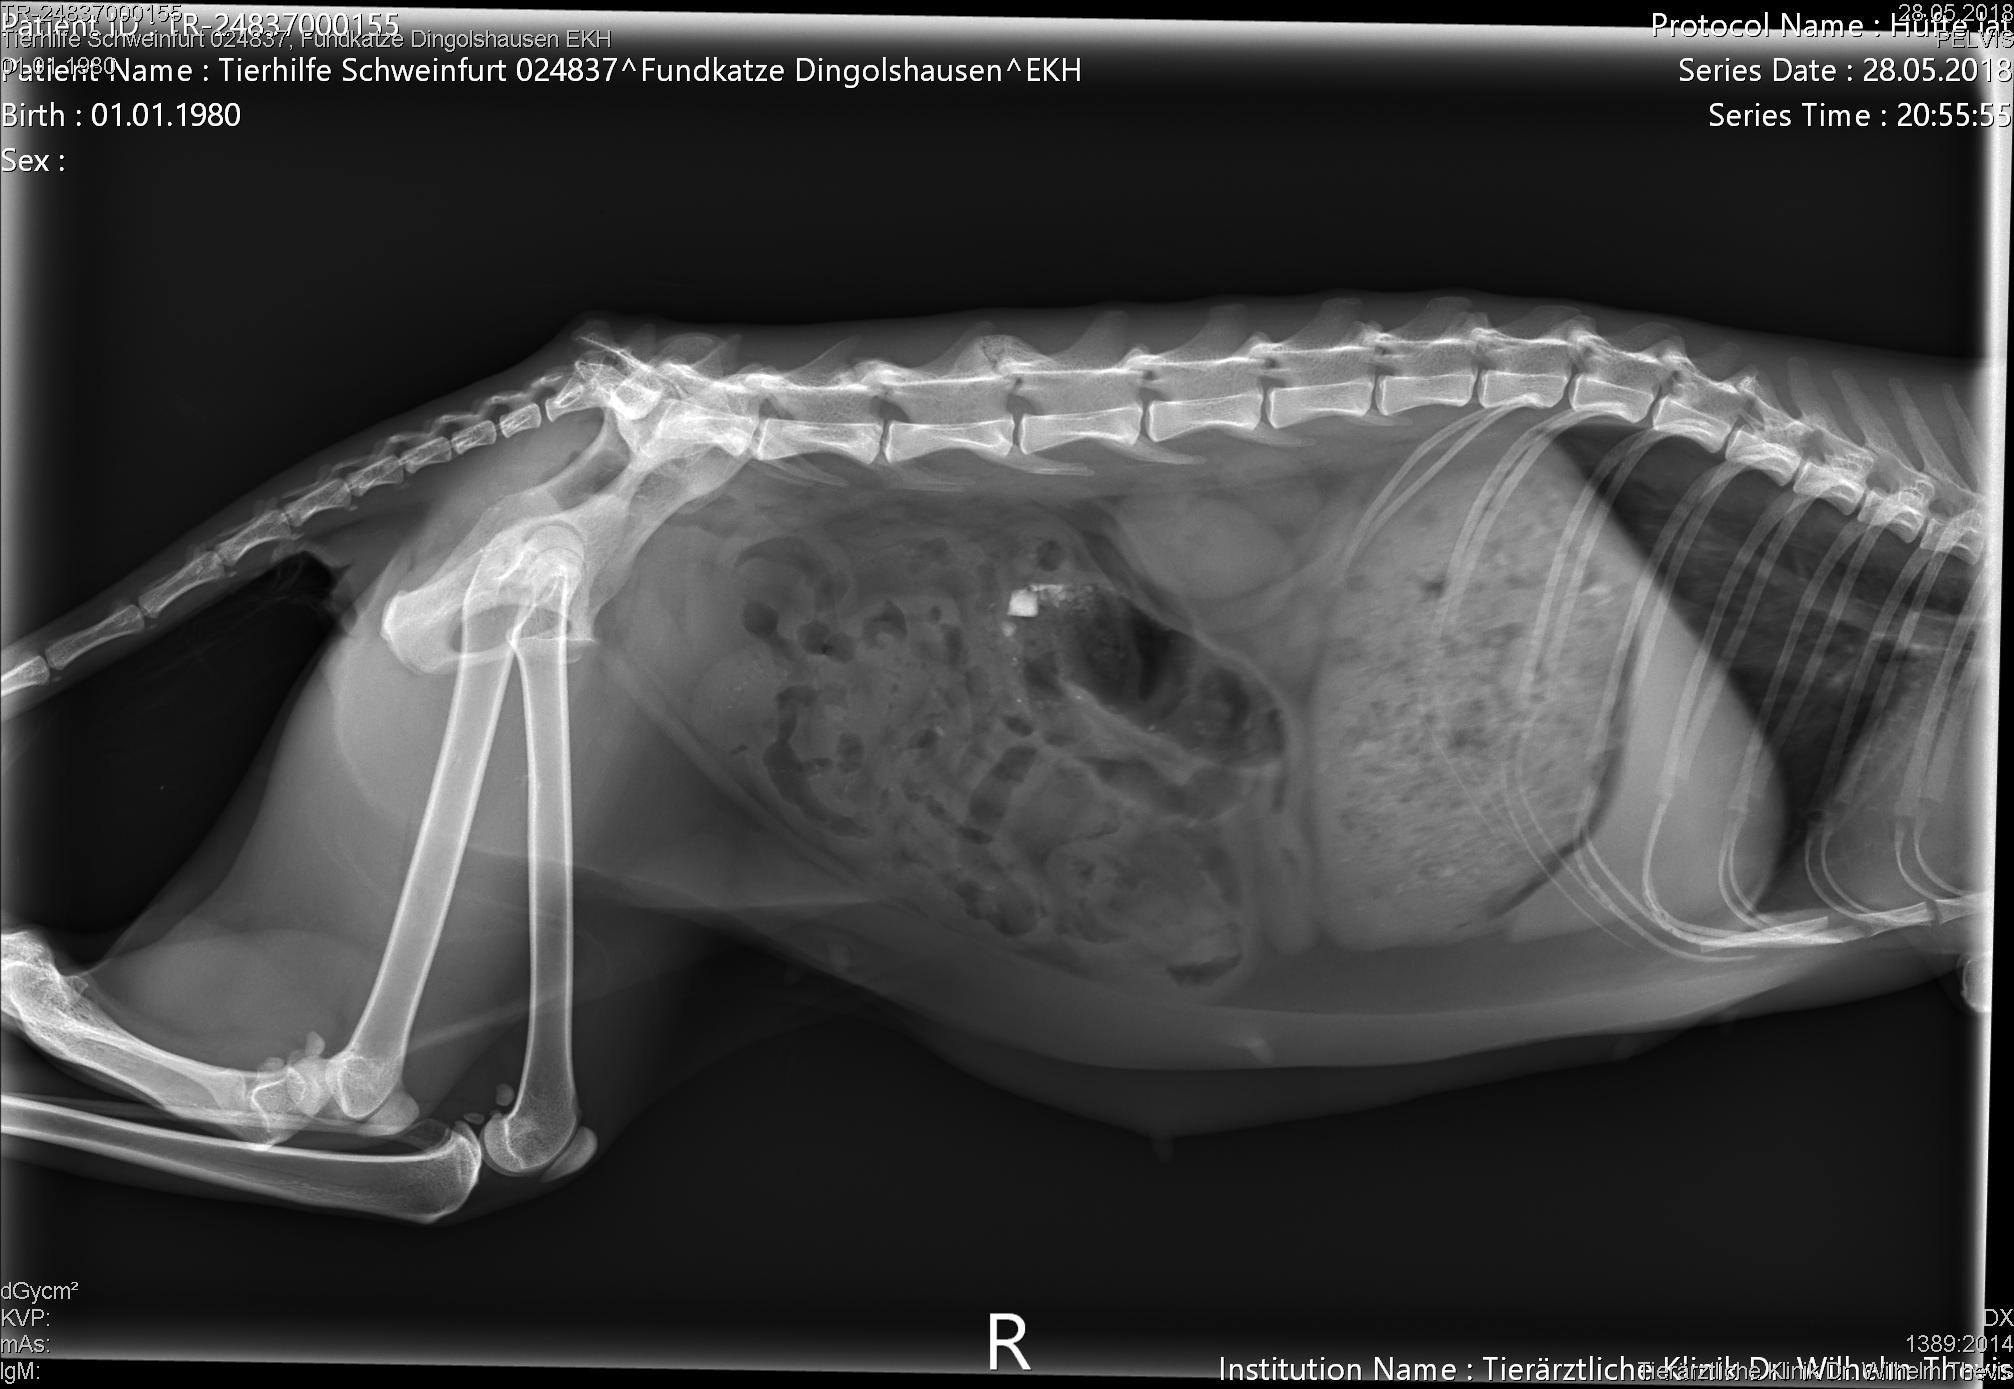

Dort stellte sich heraus, dass die Mieze tatsächlich einen Unfall hatte, jedoch schon vor einer Weile. Die Knochen sind jedoch leider alle krumm zusammen gewachsen, da sie wohl nie behandelt wurde :(. Nicht auszumalen, was die Süße an Schmerzen durchleiden musste. Außerdem fiel in der Tierklinik ihr schlechter Zustand auf: Sie war abgemagert, litt unter flüssigem Durchfall und war voller Parasiten.